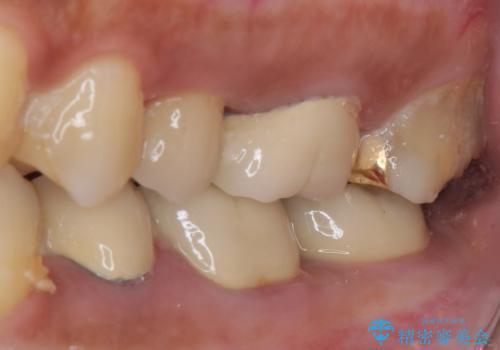

- 食事中にしばしば痛みを感じるとのことで来院された患者様です。

診査をしたところ、レントゲン写真よりとても大きなむし歯があることが分かりました。

虫歯が歯髄腔(神経の部屋)に達している可能性が非常に高かったため、炎症を起こしている神経組織を部分的に切除し、歯根部分の神経組織を保存する治療法が望ましいと考えられました。

処置開始前から神経組織を部分的に除去する可能性が高いことが分かっていたため、ラバーダムなどの環境を整え、無菌的環境下にて処置を進めて行きました。

虫歯は深くまで進行しており、歯冠部の神経から出血が認められました。神経を部分的に除去したところ出血が治まったので、生体親和性の非常に高いセメントにて充填し、仮封をしました。

後日状態を確認したところ、残された神経に異常がなかったため、セラミッククラウンにて補綴治療を行いました。